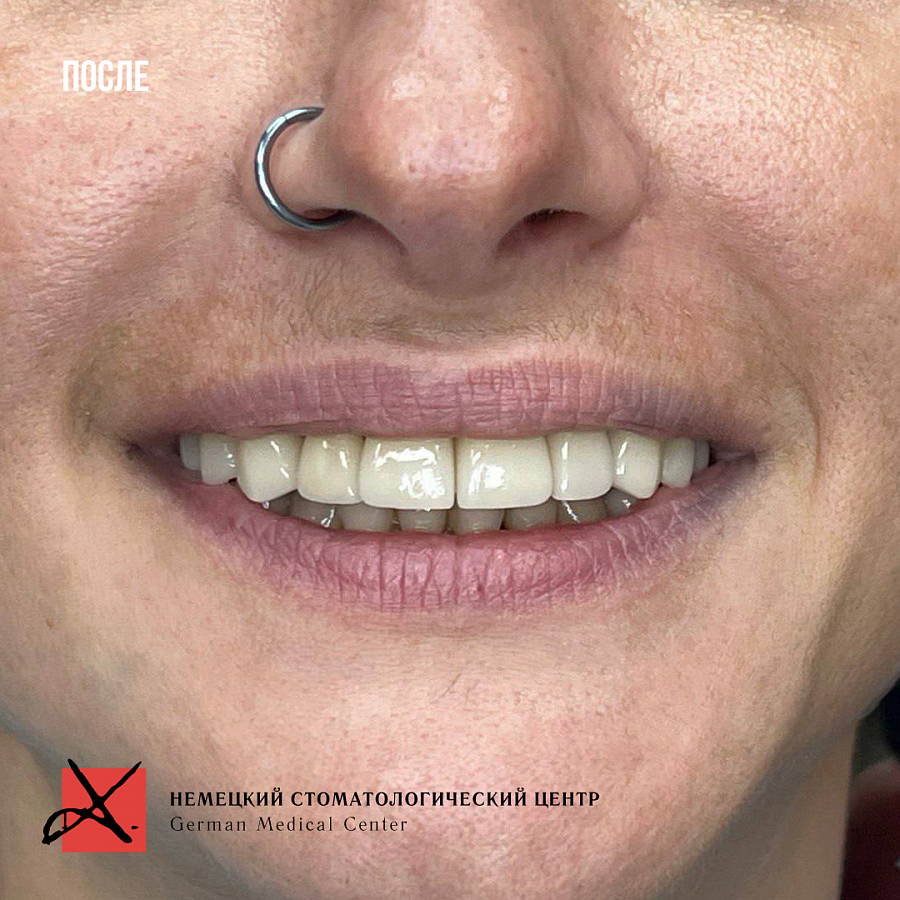

Все проблемы решили грамотным тотальным протезированием. Челюсть приняла правильное положение, ушла боль и дискомфорт, а вместе с ними и страх.

Результат лечения